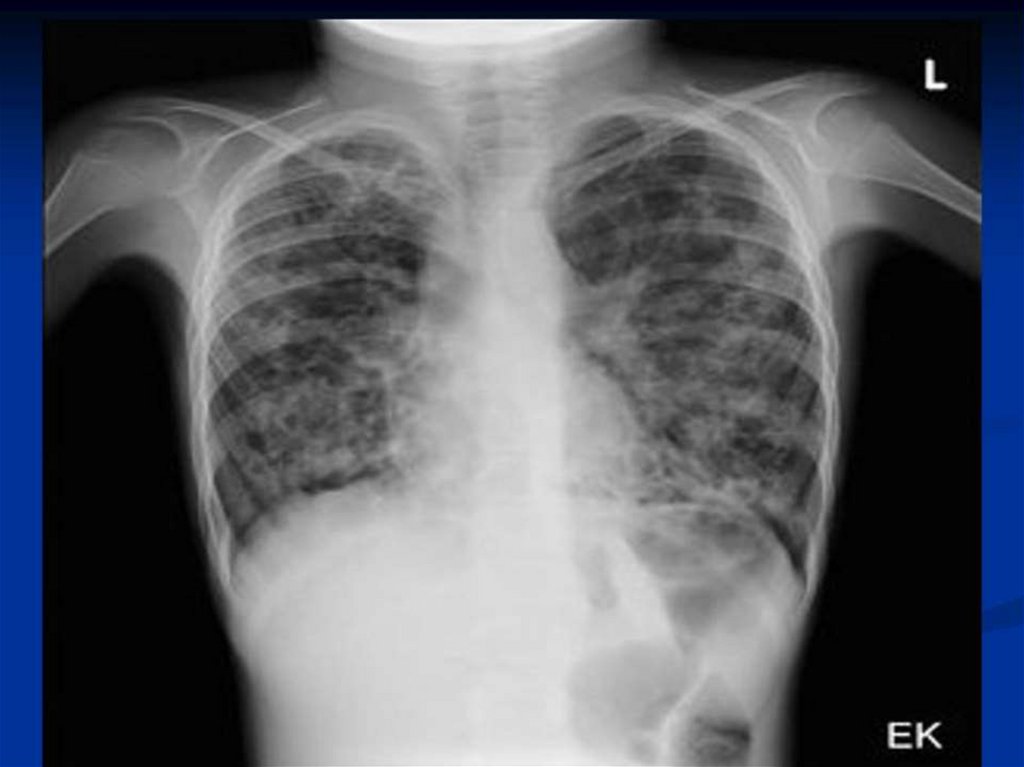

Хронические неспецифические заболевания лёгких у детей

Хронические неспецифические заболевания легких у детей